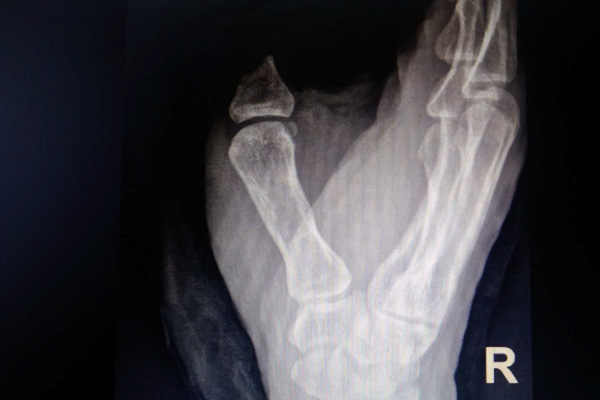

救護車的呼嘯劃破了寧靜的夜空,7月21日晚7時左右,我院急診科收治一名由外院轉至我院的“右手拇指旋轉撕脫離斷傷”患者,該患者工作中右手不幸被機器卷入,其右手拇指被卷入皮帶輪,導致右手拇指從第一掌指關節處完全離斷、近節指骨骨折、肌腱、血管、神經完全撕脫抽出,并伴有大量出血,痛苦萬分,情況十分緊急。

據我院骨二科秦小勇副主任醫師介紹,患者下午3點鐘受傷,送至外院被告知無法治療后,輾轉來到我院已經是晚上7點多,耽誤了不少寶貴時間,這種程度的拇指撕脫、離斷傷,盡早再植是唯一可能恢復拇指功能的救治措施,離斷的手指越早進行手術,再植成功的幾率就越大,必須分秒必爭。

“斷指再植成活的前提是建立有效的血運,吻合的動脈、靜脈血管暢通。患者的拇指損傷實在是太嚴重了,肌腱、神經撕脫約30多厘米,動脈、靜脈血管因撕脫傷同樣損傷嚴重,我們面臨巨大的挑戰。根據探查的嚴峻結果,專家們在手術臺上再次組織了討論,調整手術方案,為斷指再植成功盡最大努力”。作為一名手外科醫生,秦小勇醫生深知右手拇指對于一位勞動者來說是多么重要,失去了拇指的右手功能將損失50%以上,那是對一位工程師、技術工人多么致命的打擊。從看到病人的那一刻起,他和他的團隊就決定要盡最大的努力保住傷者的拇指。手術中容不得一絲馬虎,專家團隊密切合作,顯微刀片在閃光、顯微縫合在穿梭,每一針線、每個縫合都是那么認真、完美,時間銘記在1個半小時后,骨折固定、肌腱神經轉位、動脈血管吻合一氣呵成,離斷拇指恢復正常血運,又在顯微鏡下經過2小時的努力,患者拇指背側的靜脈血管全部完成吻合,拇指顏色紅潤、血運良好,手術順利結束,患者被安全送回了病房。